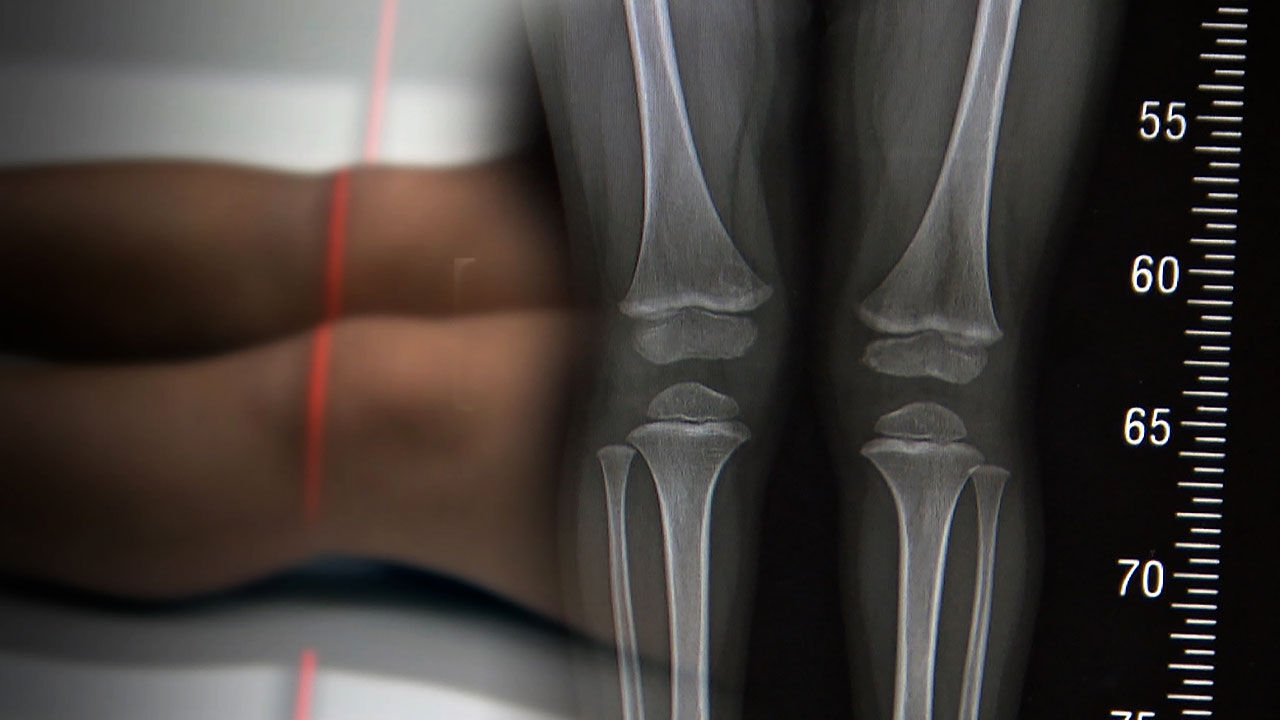

요즘 아이들 키에 민감한 부모들이 많아지면서, 성장보조제나 영양제를 먹는 아이들도 늘어나고 있는데요. 하지만 정작 키 크는 데 제일 중요한 잠을 잘 자고, 규칙적으로 운동하는, 이런 기본적인 생활 습관은 제대로 지켜지지 않고 있었습니다.

부모 10명 중 3명은 아이에게 '성장 보조제'나 영양제를 먹인 적이 있다고 답했고, 성장호르몬 주사를 맞힌 경우는 100명 중 5명 정도였습니다.

[이해상/아주대병원 소아청소년과 교수 (대한소아내분비학회 홍보이사) : 충분한 수면, 균형 잡힌 식사, 규칙적인 운동이 가장 중요한 핵심 요소가 되겠고 이런 성장 보조제라든지, 성장 호르몬 주사라든지 이런 것들에 대해 무분별하게 사용하는 것은 주의가 필요할 수 있겠습니다.]